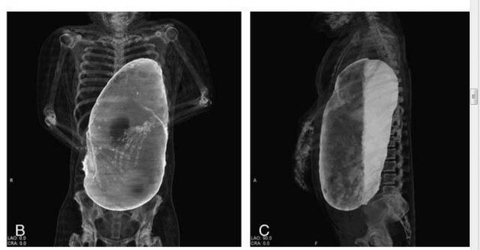

20인분 넘게 먹고 사망한 사람의 X 레이 사진

위가 40~50배로 커져 심장으로 들어가는 혈관을 눌러 혈류장애로 사망